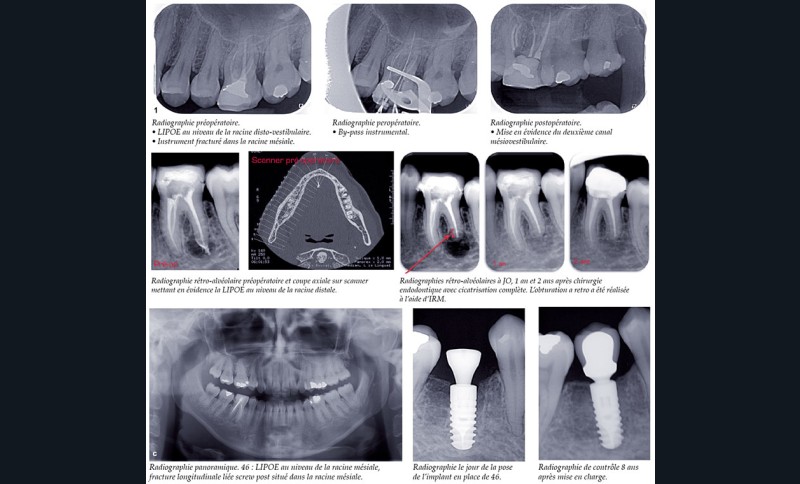

Les thérapeutiques endodontiques et implantaires ont un objectif commun : permettre une restauration fonctionnelle et esthétique ayant la pérennité la plus longue possible. L’apparition et le développement des thérapeutiques implantaires depuis 50 ans ont constitué indéniablement un changement dans les mentalités des chirurgiens-dentistes et les possibilités de traitements offertes aux patients. Il est admis que la meilleure solution pour le remplacement d’une dent unitaire absente est une solution implantaire. Mais, qu’en est-il d’une dent présente, traitée endodontiquement avec un échec clinique et/ou radiologique (fig. 1) ?